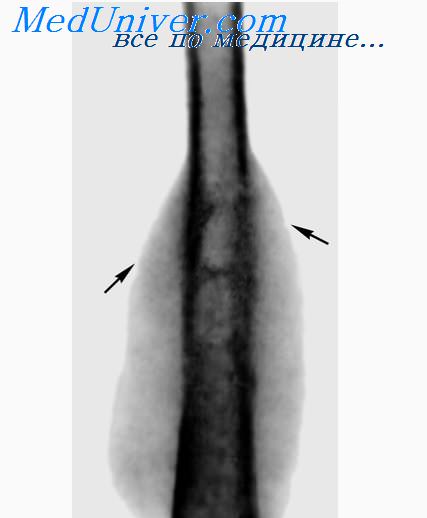

Медицинские аспекты заболеваний: рентгенологическая картина туберкулеза костей

Раздел: Снимки-откровения